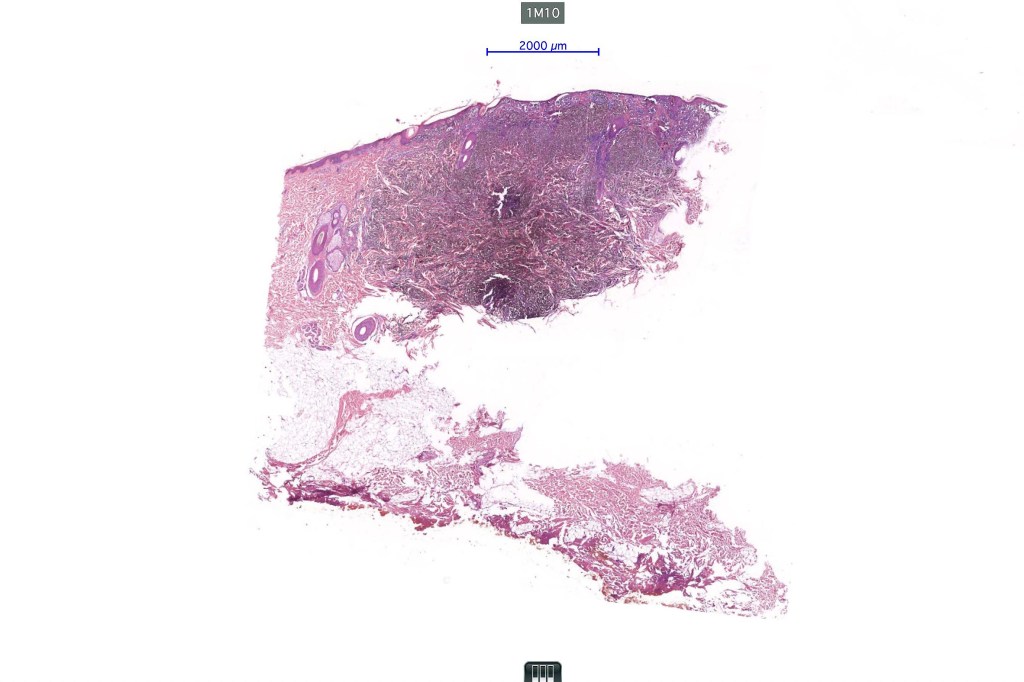

1.typical melanoma in the superficial aspect overlying a deep penetrating nevus-like deeper component

2. typical epithelioid melanoma in the superficial aspect associated with very marked perivascular and appendageal spread giving rise to a plexiform appearance

4. melanoma which shows a deep penetrating architecture although the cytology remains epithelioid throughout